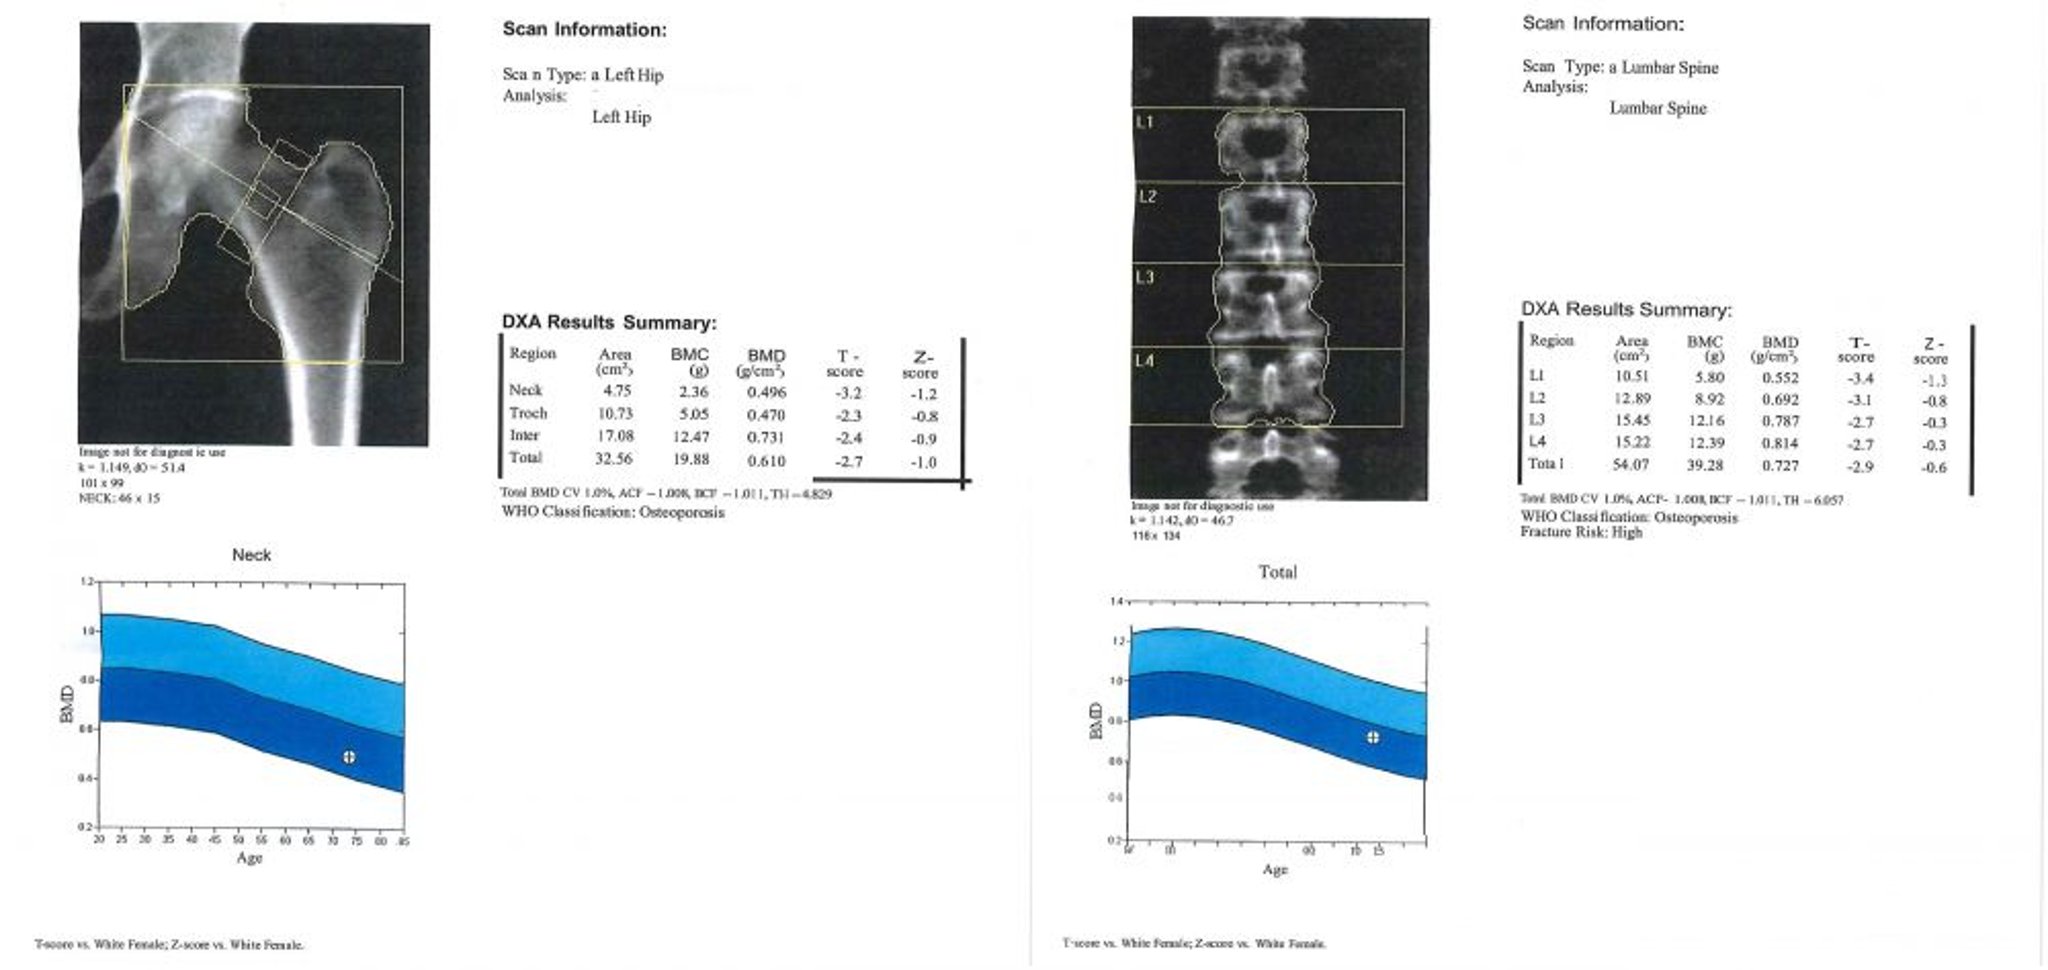

DXA Scan

This image is an example of a DXA scan report. In the graph, the area in light blue represents osteopenia and the area in dark blue represents osteoporosis. The patient’s values are represented by the “+” sign inside the circle in each graph.

Image courtesy of Marcy B. Bolster, MD.